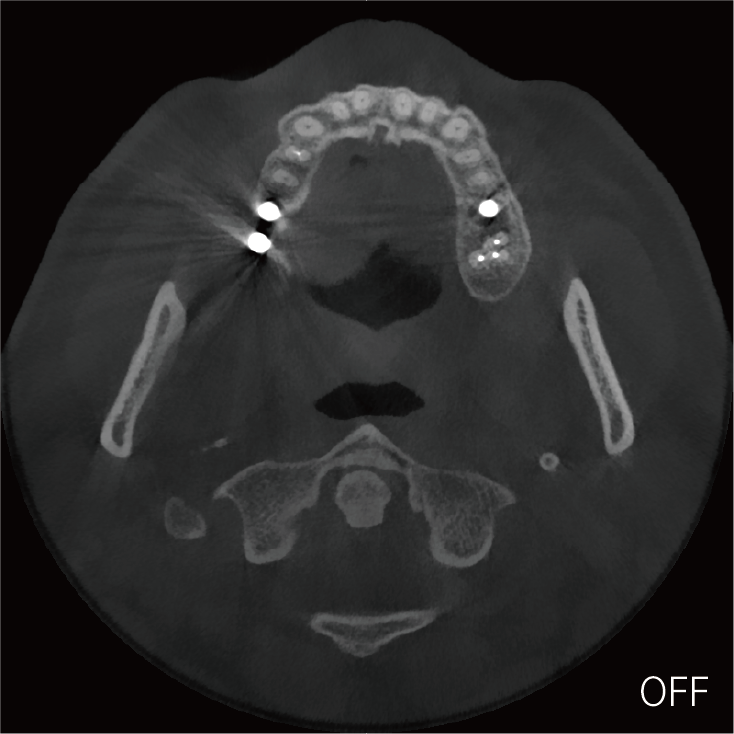

超能去伪 至臻影像

临床样片